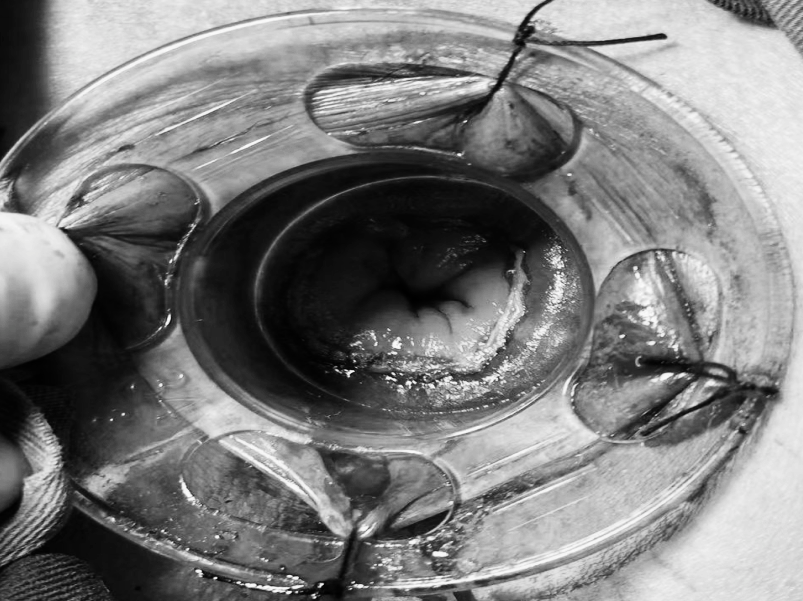

您是否正在经历 肛周肿痛、瘙痒的困扰? 是否发现过便血 或是有小肉球脱出来? 是不是因为觉得尴尬 所以一直拖着没去看? …… 这些难言之隐的背后 往往是痔疮、肛裂等 肛周疾病的信号 这些常见问题,往往与我们的日常生活习惯息息相关:长时间坐着不动、如厕时久蹲、饮食中缺乏蔬菜水果都可能增加患病风险。预防的关键在于主动调整: ✔饮食要“润”:多吃蔬菜、水果、粗粮,保证饮水,让大便保持通畅松软。 ✔久坐要“动”:每隔一小时起身活动几分钟,减轻肛周压力。 ✔如厕要“快”:减少如厕时间,避免久蹲和过度用力。 ✔清洁要“轻”:便后保持清洁,用温水冲洗或柔软纸巾轻拭。 养成良好的生活习惯,是守护肛周健康的第一道防线。 目前,治疗这类疾病的方法有很多。在贵州航天医院普外科,我们在常规诊疗基础上,进一步融入了中医调理的优势,为您提供一种更注重恢复过程中的舒适度、也更关注身体的整体调理特色方案——中西医结合治疗肛周疾病,希望能帮助您更安心、更顺畅地解决难言之隐。 【中西医结合,优势互补】 ※西医精准明确,技术微创:借助电子肛肠镜等设备清晰诊断,并运用PPH(吻合器痔上黏膜环切术)、TST(选择性痔上黏膜吻合术)等微创手术技术,精准处理病灶,创伤小、出血少。 ※中医整体调理,促进康复:通过内服外用中药,协助术后消肿止痛、促进创面愈合,并帮助调整内在体质,减少复发。 【中西医结合诊疗的优势】 ▶术前可中医干预:对处于急性炎症期的患者,先行中药坐浴、外敷等缓解肿痛,创造更好手术条件,部分患者可能因此免于手术。 ▶术中微创精准:由经验丰富的肛肠外科医生操作,注重保护正常功能组织。 ▶术后康复加速: •中药内服调理:根据个人体质开具药方,促进恢复。 •中药坐浴外治:使用科室配置的洗剂,帮助保持清洁、缓解疼痛、舒适伤口。 •专业西医护理:配合规范的伤口换药与护理,保障愈合过程顺利。 •多模式镇痛:采用中西药结合的多种镇痛方式(如口服、外用、中药制剂等),有效缓解术后疼痛,帮助您更舒适、安心地度过恢复期。 适合以下常见肛周疾病患者: 各期痔疮(内痔、外痔、混合痔)、肛裂、肛周脓肿、肛瘘、直肠息肉、肛周湿疹、肛门尖锐湿疣、肛乳头瘤、肛门狭窄、肛门失禁等。 温馨提示: 1.肛周疾病重在早发现、早干预,请不要因羞涩而延误最佳治疗时机。 2.本文仅为疾病科普与诊疗介绍,不能替代任何专业的医疗建议,如有任何健康问题,请务必及时咨询并遵从专业医生的诊疗意见。 注:部分图片来源于网络,如有侵权,请联系删除。 贵州航天医院普外科专家简介 高大勇 普外科(肛肠外科)学科带头人、名誉主任,主任医师、教授 临床擅长:对中西医结合诊治肛肠学科各种常见病、多发病及疑难杂症等具有丰富的临床经验。 原遵义市第一人民医院(遵义医科大学第三附属医院)、遵义市中医院肛肠科主任。中华中医药学会肛肠分会常委,全国中医肛肠学科名专家,中国健康促进与教育协会肛肠分会常委,中国康复医学会肛肠疾病康复专业委员会常委,中国民间中医医药研究开发协会肛肠分会副秘书长,中国医师协会中西医结合肛肠医师专业委员会常委,国家二级心理咨询师,贵州省第一批中医名医工作指导老师,遵义市名中医,遵义市肛肠学会会长,遵义市肛肠质控中心名誉主任,遵义市中西医结合学会名誉会长,遵义市健康科普专家,原贵州省中西医结合学会肛肠分会副主任委员、贵州省中医肛肠质控中心副主任、遵义市医学会医疗鉴定委员会专家、遵义市卫生系列高评委。发表论文30余篇,主编和参编医学著作5本,主持省级科研课题2项、市级科研课题2项、院级科研课题1项。 梁 跃 普外科党支部书记、主任,主任医师 临床擅长:对普外科各类肿瘤手术具有丰富的临床经验。 毕业于遵义医学院,遵义市医学会小儿外科学分会常务委员,遵义市肛肠协会理事,遵义市医学会核医学分会(第二届)委员会委员;荣获第三期“黔医人才计划”优秀学员称号;主持市级课题1项,完成省级课题1项,在国内各类刊物上发表论文10余篇。 钱科洪 民盟盟员,普外科副主任医师 临床擅长:从事普外科临床工作30余年,对各类普外科疾病的诊治、乳腺、甲状腺、胃十二指肠、结直肠等疾病及疑难杂症具有丰富的临床经验。 毕业于遵义医学院临床医疗系,2009年前往中山大学附属第一医院微创外科进修学习,在国内各专业期刊发表论文数篇。 贵州航天医院普外科简介 基本情况 贵州航天医院普外科成立于1968年,前身属于航天部O61基地3417医院外一科,1998年3417医院、3427医院合并后更名为普外科,下设胃肠外科、肛肠外科2个亚专业科室,拥有在全市较为先进的专科设备和技术,是中国疝病专科联盟单位,贵州医科大学附属医院胃肠外科专科联盟单位。开放床位40张,配备医护人员21人。 专科特色 普外科致力于胃肠及肛肠疾病的外科临床诊治及科研,以腹腔镜微创外科技术为本,形成以快速康复治疗胃肿瘤、结直肠肿瘤、小肠肿瘤、直肠脱垂、肥胖病、急腹症、各类疝、痔、瘘等专科特色,同时注重胃肠疾病尤其是结直肠恶性肿瘤的基础研究和临床转化研究,总体诊断和治疗水平在区域同级医院居于领先水平。 开展手术:腹腔镜下胃癌根治术,腹腔镜下袖状胃切除术,腹腔镜下胃肠道间质瘤切除术,腹腔镜下结、直肠癌根治术,胃癌、结直肠癌的精准治疗,腹腔镜下小儿疝气、成人疝修补术,腹腔镜下阑尾手术,内痔的硬化注射治疗及痔疮的微创治疗:ATH、PPH、TST,直肠脱垂的各种手术治疗,难治性伤口VSD技术,鼻胃肠管、肠梗阻导管置入术,肛肠术后间歇性导尿技术,并引进了中医适宜技术,也为各种化疗患者提供输液港安装,提高患者就医体验。 腹腔镜下腹股沟疝 无张力修补术 腹股沟疝里金斯坦 (Lichtenstein)手术 PPH微创术治疗环状混合痔 黏连性或炎性肠梗阻-肠梗阻导管 腹腔镜袖状胃切除 腹腔镜阑尾切除术 腹腔镜阑尾肿瘤切除术 腹腔镜下结肠癌根治术 诊疗范围 胃肿瘤、结直肠肿瘤、小肠肿瘤、肥胖症、各类急腹症、腹部外伤、腹壁疝、便秘、直肠脱垂、痔疮、肛瘘、肛裂等胃肠、肛肠外科疾病。 END